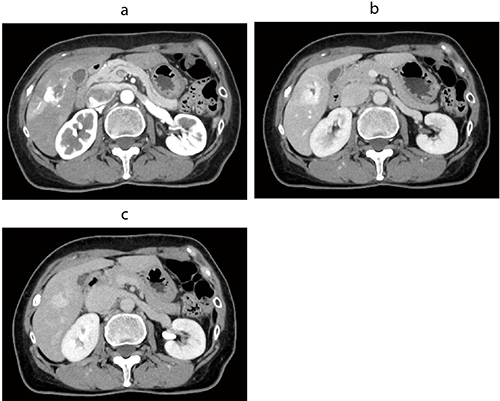

図1 低線量胸部CT

高速スキャン、AiCE-i適用で胸部を3.5秒、約1.0mSvで撮影〔k:0.014(ICRP Publication 102)、Effective Dose=DLP×0.014〕